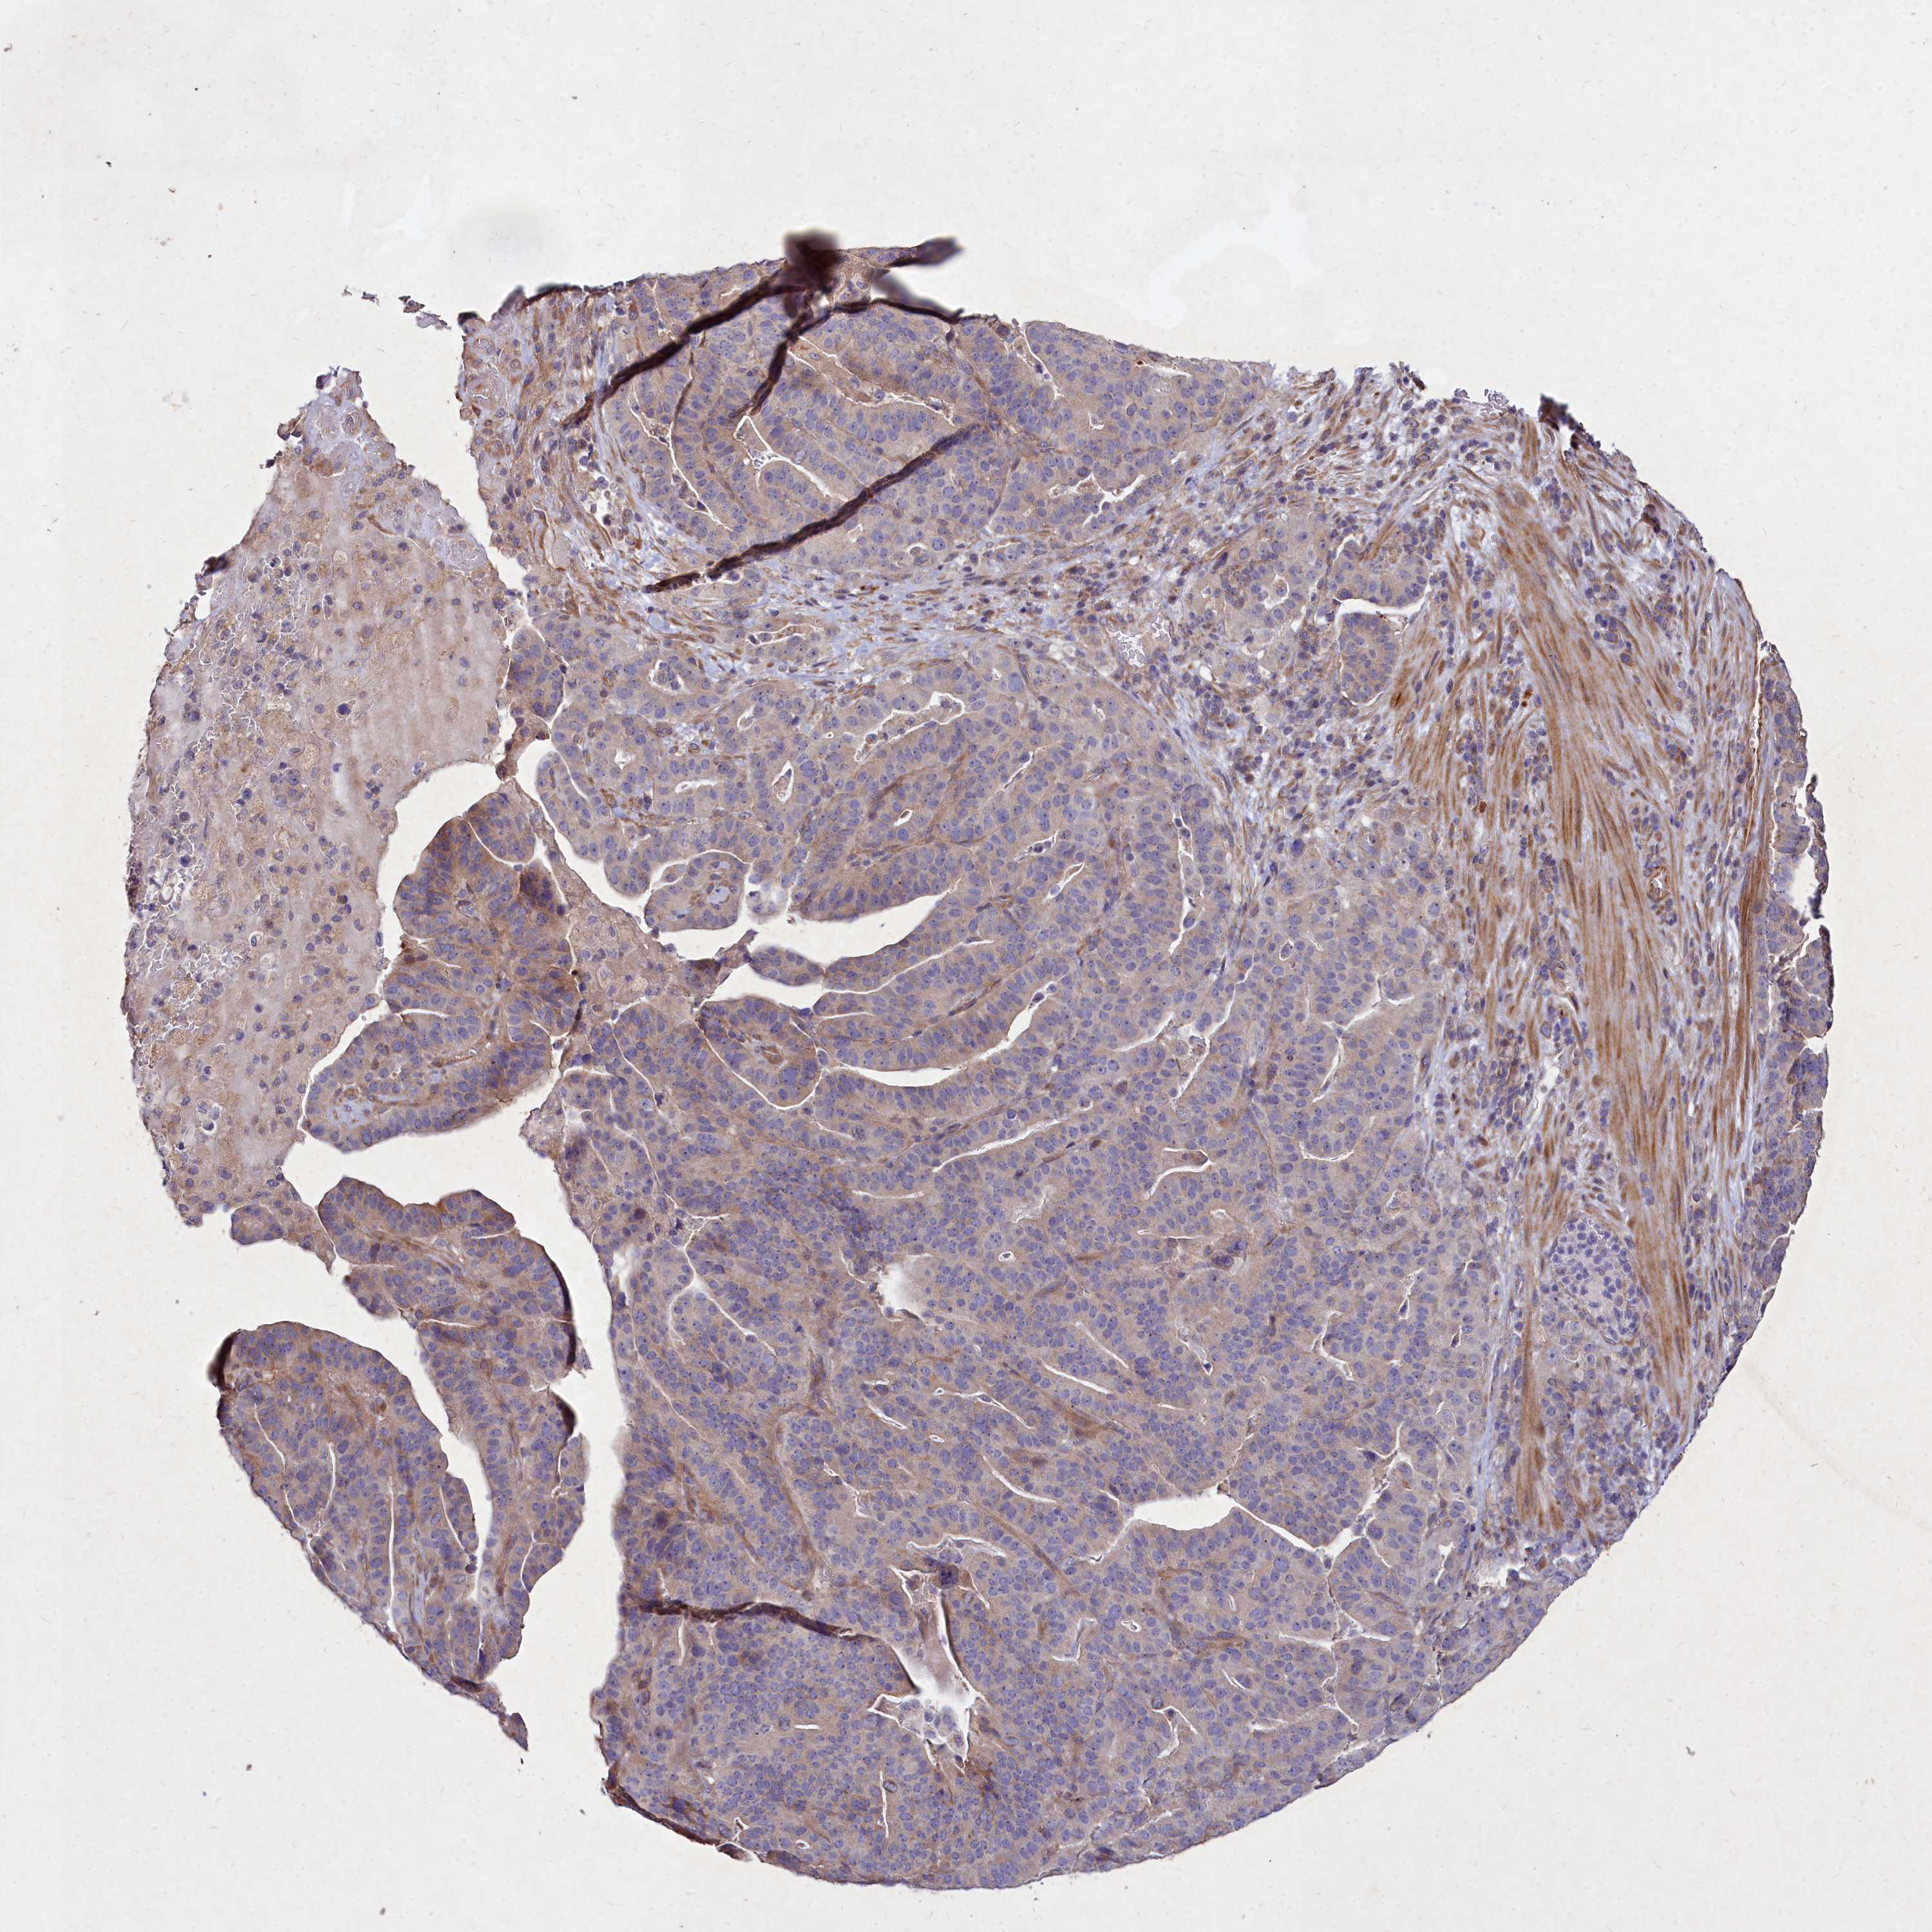

STOMACH CANCER - Protein expressioni

A mouse-over function shows sample information and annotation data. Click on an image to view it in a full screen mode. Samples can be filtered based on level of antibody staining by selecting one or several of the following categories: high, medium, low and not detected. The assay and annotation is described here.

Note that samples used for immunohistochemistry by the Human Protein Atlas do not correspond to samples in the TCGA dataset.

Antibody stainingi

Antibody staining in the annotated cell types in the current human tissue is reported as not detected, low, medium, or high, based on conventional immunohistochemistry profiling in selected tissues. This score is based on the combination of the staining intensity and fraction of stained cells.

Each image is clickable and will lead to virtual microscopy that enables deeper exploration of all samples and also displays staining intensity scores, fraction scores and subcellular localization as well as patient and tissue information for each sample.

Antibody HPA045495

Staining

High

Medium

Low

Not detected

Intensity

Strong

Moderate

Weak

Negative

Quantity

>75%

75%-25%

<25%

None

Location

Nuclear

Cytoplasmic/membranous

Cytoplasmic/membranous,nuclear

Adenocarcinoma, NOS